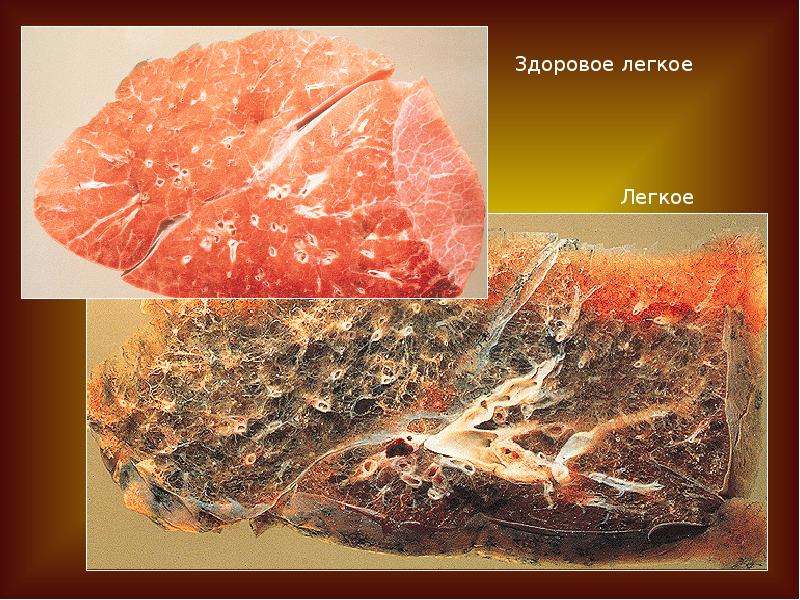

Здоровый образ жизни: Влияние курения